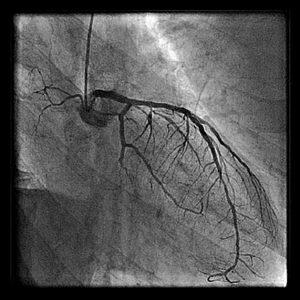

画像のPCI-1、2、3は1stPCIで1年後のAMI、resque後、stenting後となっています。

resqueでは血栓が引けたように記憶しています。